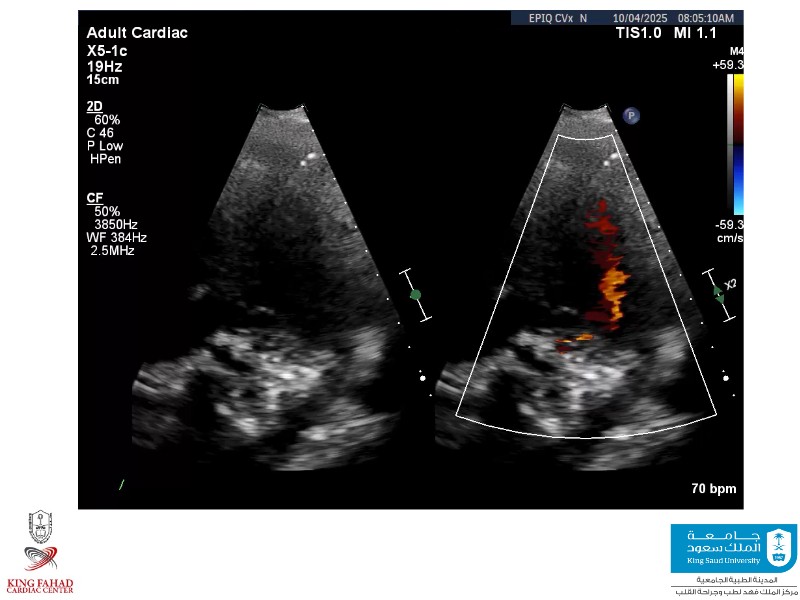

This session helps you anticipate and address complex scenarios such as mitral valve-in-valve, TAV-in-SAV, and valve-in-valve-in-valve procedures. Learn from expert case discussions that explore procedural strategies, technical challenges, and best practices to optimize outcomes in redo structural heart interventions.